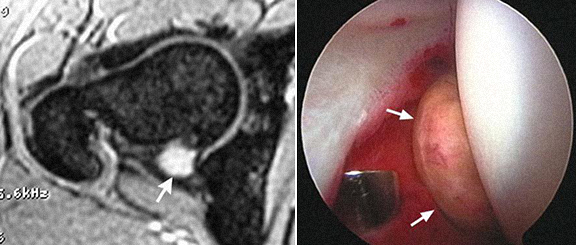

1 - Rotura do labrum 2 – Delaminação da cartilagem